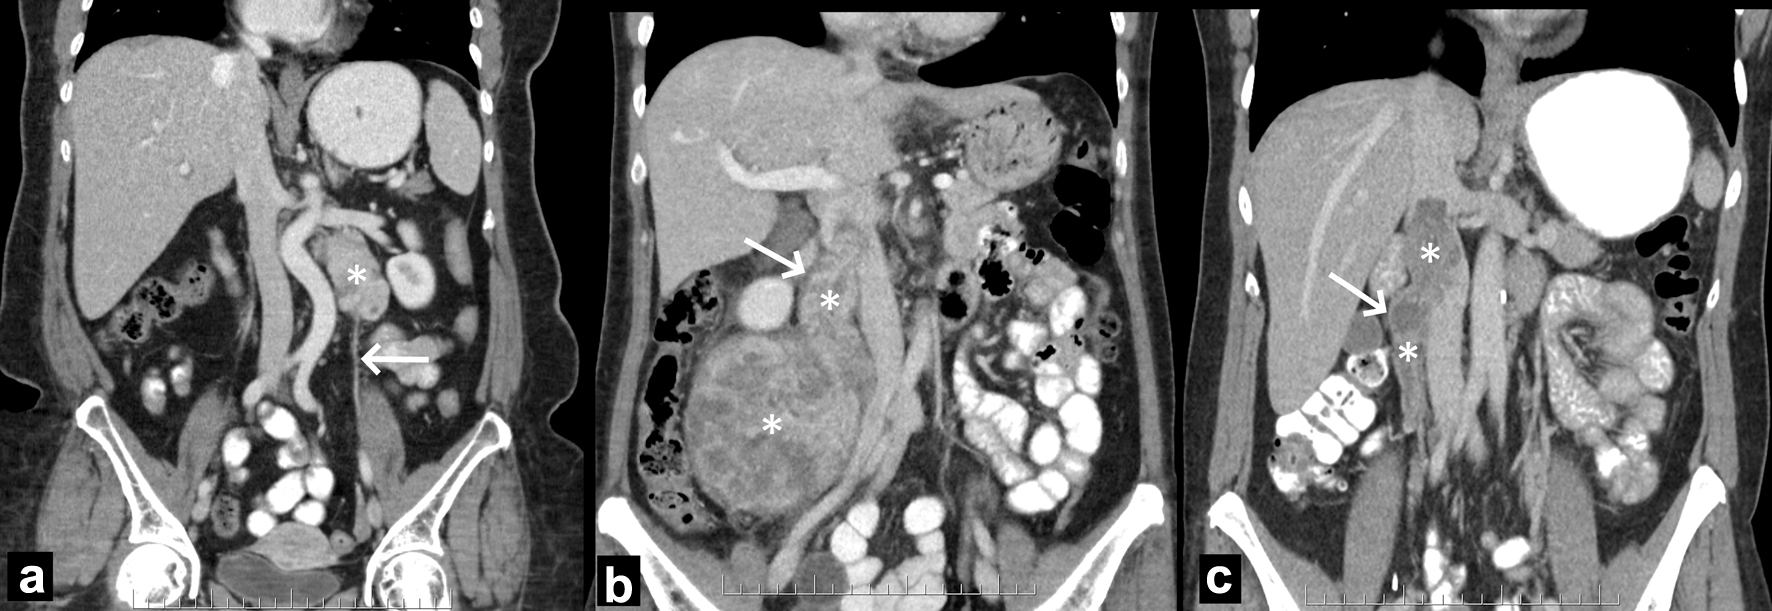

Criteria related to determining the exact vascular/organ origin of LMS were derived a priori in consensus by two radiologists (KK and CM) who were members of sarcoma tumor board and had experience in sarcoma imaging in two separate institutions. Details of the determination of the primary site of tumor and imaging review are outlined in Supplementary Material 1 (www.wjon.org). The radiologists reviewed 15 random vascular LMS cases consensus to standardize and synchronize the method of review. All imaging available were then reviewed by one of the radiologists (21 years in practice) with indeterminate lesions reviewed by a second radiologist (32 years in practice). Pathological and intra-operative findings were not used to designate the origin of tumors. Examples of designation of venous origin are depicted in Figure 1.

![]() Click for large image | Figure 1. Illustration of designation of tumor origin in three different patients. (a) Left ovarian vein LMS. The left retroperitoneal tumor (asterisk) is located caudally to the left renal vein and laterally to the aorta. The left ovarian vein (arrow) extends into and from the tumor (not shown). (b) Right ovarian vein LMS. The right retroperitoneal tumor (asterisks) extends up the right ovarian vein (arrow) and into the IVC. (c) IVC IIA. The purely intravascular tumor (asterisks) lies within the right ovarian vein (arrow) and IVC, at and below the left renal vein. Because the tumor had a wider diameter in the IVC than in the ovarian vein, the former was designated as site of origin. IVC: inferior vena cava; LMS: leiomyosarcoma. |